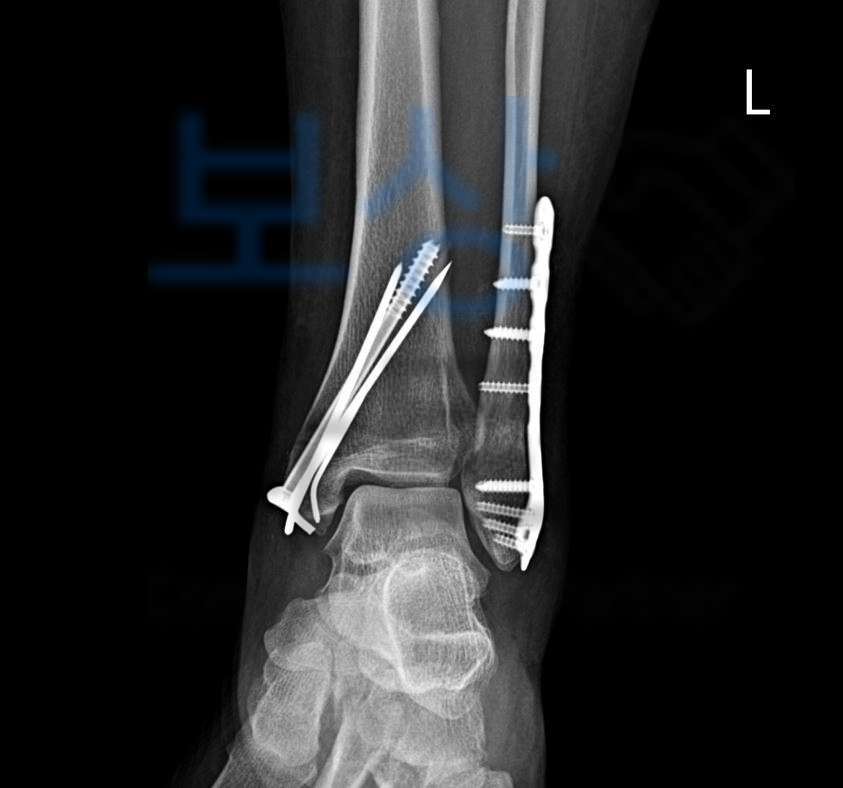

좌측 족관절의 외복사골절,

양측의 복사 골절, 좌측관절 양과골 골절 진단을 받으셨습니다ㅠㅠ 보상파트너는 의뢰인께 보험내역 확인을 요청드렸고, 가입하신 보험증권에서 상해후유장해 항목을 찾으셨습니다.